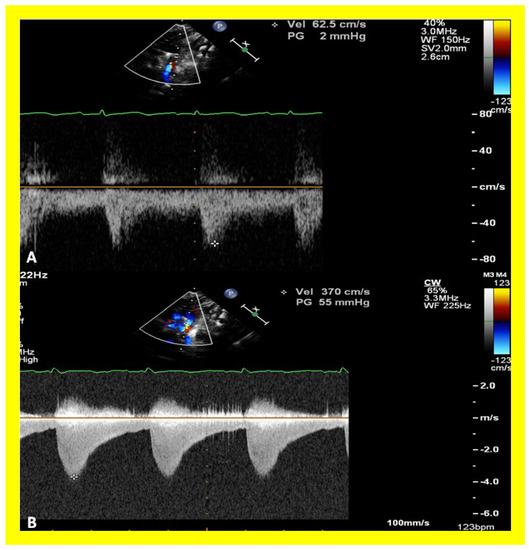

Then, the ventricular septum is evaluated; the ventricular septum is intact in most Type Ia cases. In children with Type I (normally related great arteries), the VSD supplies the pulmonary blood flow (Figure 10) while in patients with Type II (transposition of the great arteries) the VSD allows the blood to flow into the systemic circuit (Figure 11; Figure 12). In Type I patients, the VSD is demonstrated by 2D (Figure 10A), and the left to right shunt across it by color (Figure 10B), pulsed and CW (Figure 10C) Doppler signals. The interrogation of the RV outflow tract and PA region should be performed; recording the peak Doppler flow velocity across the RV outflow tract and the pulmonary valve is helpful in identifying obstruction across these sites. The Doppler data from the VSD and RV outflow tract are also helpful in the estimating of PA pressures. In Type I babies, the 2D size of the VSD and the peak Doppler flow velocity across it are useful in quantifying the size of the VSD (Figure 10). The higher the VSD Doppler flow velocity, the smaller the defect. However, in patients with pulmonary hypertension or severe infundibular or valvar pulmonary stenosis, the VSD Doppler velocities are not reflective of the size of the VSD. Barring these exceptions, RV and PA systolic pressure may be estimated using a modified Bernoulli equation (RV/PA systolic pressure = systolic blood pressure – 4V2).

Figure 22. Selected echocardiographic video frames demonstrating pulmonary artery band (PAB) with narrow diameter of 2.9 mm by 2D (A) and by color flow (B) and a high gradient (81 mmHg) by continuous wave Doppler (C) are shown.

Applsci 11 09472 g022

Figure 23. Selected echocardiographic video frames demonstrating pulmonary artery band (PAB) with narrow diameter by color flow (A) and a high gradient (88 mmHg) by continuous wave Doppler (B) are shown.

Applsci 11 09472 g023

In patients who had banding of the PA, echo-Doppler studies should be scrutinized to demonstrate the banded PA diameter (Figure 22A,B and Figure 23A) and peak Doppler flow velocity across the banded PA (Figure 22C and Figure 23B); high Doppler velocity across the band (Figure 22C and Figure 23B) would suggest effective palliation. Low gradients and ineffective control of CHF may require tightening of the band; echo-Doppler evaluation is useful in making such an assessment.